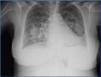

A chest x-ray taken when the patient was hospitalised indicated bilateral increased densities with butterfly patterns (Figure 1), and the abdominal ultrasound detected homogeneous hepatosplenomegaly and kidneys with normal size and morphology, with no dilation of the urinary tract.

With the available data indicating rapidly progressing renal failure, anaemia, and bloody sputum, as well as the increased densities in the chest x-ray, we suspected extracapillary glomerulonephritis and started treatment with 500mg pulses of 6-methylprednisolone. We also started diuretic treatment with a positive response, but with no improvement in renal function, and so we also started renal replacement therapy with haemodialysis.

Figure 1. Chest x-ray obtained upon patient hospitalisation